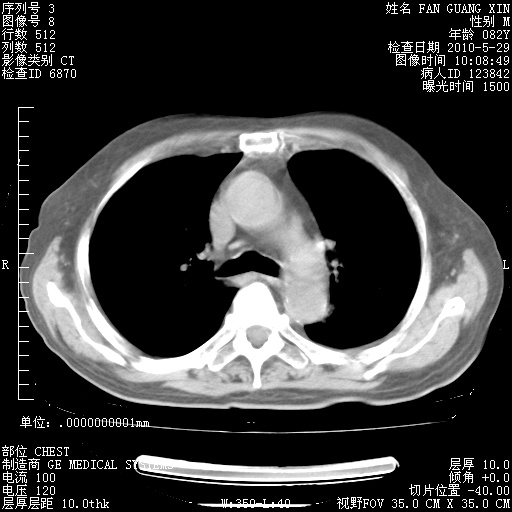

治疗3周后的肺部CT纵隔窗

再治疗10天后的肺部CT

再治疗10天后的肺部CT 纵膈窗

阅读此次胸部CT,肺间质渗出性改变较入院时有吸收。目前从体温、白细胞、中性分叶明显增高,肯定存在细菌感染(发生医院感染哦,若无消化道及泌尿系统等感染的依据,肺部感染可能大)。若你院头孢哌酮舒巴坦钠耐药率较高,同意你的方案,若48小时体温仍高,可考虑使用碳青霉稀类抗菌药物,同时可予超声雾化、注意滴数时加大液体量。白蛋白33.30g/L较低哦,需加强营养等支持治疗。